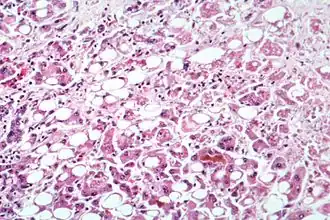

Microscopie

Une hépatite chronique est une pathologie nécrotico-inflammatoire du foie, de sévérité variée, excluant les maladies biliaires (cholangiopathies), la maladie alcoolique (hépatopathie alcoolique) et les stéatohépatites.